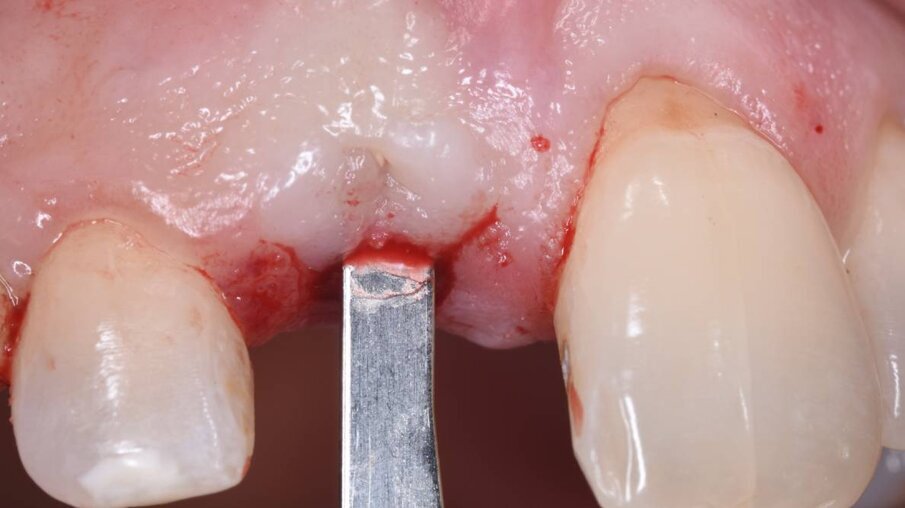

Dopo anestesia plessica con articaina 1:100.000, senza incidere le papille mesiali e distali, viene delicatamente estratto l’1.1 con strumenti piezoelettrici preservando la corticale buccale presente (indispensabile per la gestione della chirurgia); dopo un’attenta toeletta chirurgica del sito si è proceduto ad una Ridge Augmentation con Socket Seal.

È stata quindi eseguita un’incisione vestibolare intrasulculare del sito senza toccare le papille, facendo scorrere la lama sul piano osseo crestale, e nella porzione più apicale dove era presente la discontinuità della corticale si è spostato la lama mesiale e distale e ancora apicale fino a ritrovare il piano osseo secondo le indicazioni della CBCT; è stato possibile così inserire una membrana in collagene suina Geistlich Bio-Gide (Geistlich Pharma AG, Wolhusen, Switzerland) opportunamente sagomata in modo che avesse un appoggio sui piani ossei (Fig. 4); all’interno dell’alveolo è stato posizionato Geistlich Bio-Oss Collagen (Geistlich Pharma AG, Wolhusen, Switzerland), osso bovino deproteinizzato con un 10% di collagene suino addizionale, materiale osteoconduttivo che oltre a essere mantenitore di spazio e scaffold per la rigenerazione ossea, funge anche da sostegno per il tessuto molle soprastante (Fig. 5). Si è quindi proceduto dopo anestesia palatale a un prelievo tramite bisturi circolare di un punch epitelio connettivale di forma tondeggiante e misure simili all’alveolo dell’1.1 da sigillare; dopo la disepitelizzazione dei margini dell’alveolo si è proceduto alla sutura del punch al di sopra del sostituto osseo con suture Vicril 6-0 (Johnson & Johnson Medical Spa, Pomezia RM, Italia) con punti staccati alle quattro estremità e sutura a materassaio esterno incrociato compressiva (Fig. 6). In questa fase la paziente è stata riabilitata con un maryland bridge in composito cementato adesivamente.